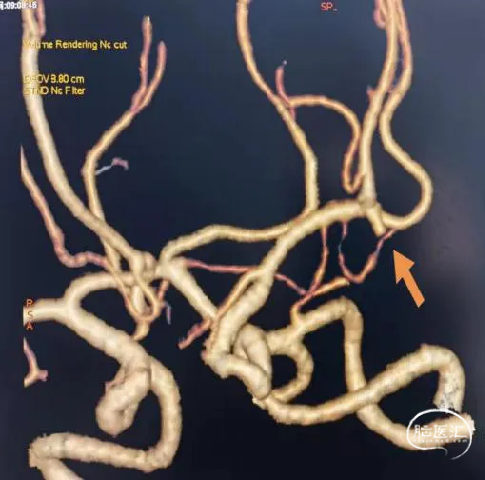

术前影像

栓塞过程

首先将Jasper®弹簧圈填入动脉瘤腔内成篮,然后向动脉瘤远端小阜填入Jasper®SS弹簧圈一枚,动脉瘤顶端小阜栓塞效果良好,并可以致密填塞小阜部分。然后填入Jasper®弹簧圈、Jasper®SS弹簧圈各一枚,造影显示胚胎型大脑后动脉保留完好,动脉瘤致密栓塞,瘤颈处无残余。

在微导丝引导下超选入海绵窦段动脉瘤瘤腔内,根据动脉瘤大小选择Jasper®SS弹簧圈一枚,栓塞过程中Jasper®SS弹簧圈经调整后可稳定填入小动脉瘤腔内。

术后即刻影像